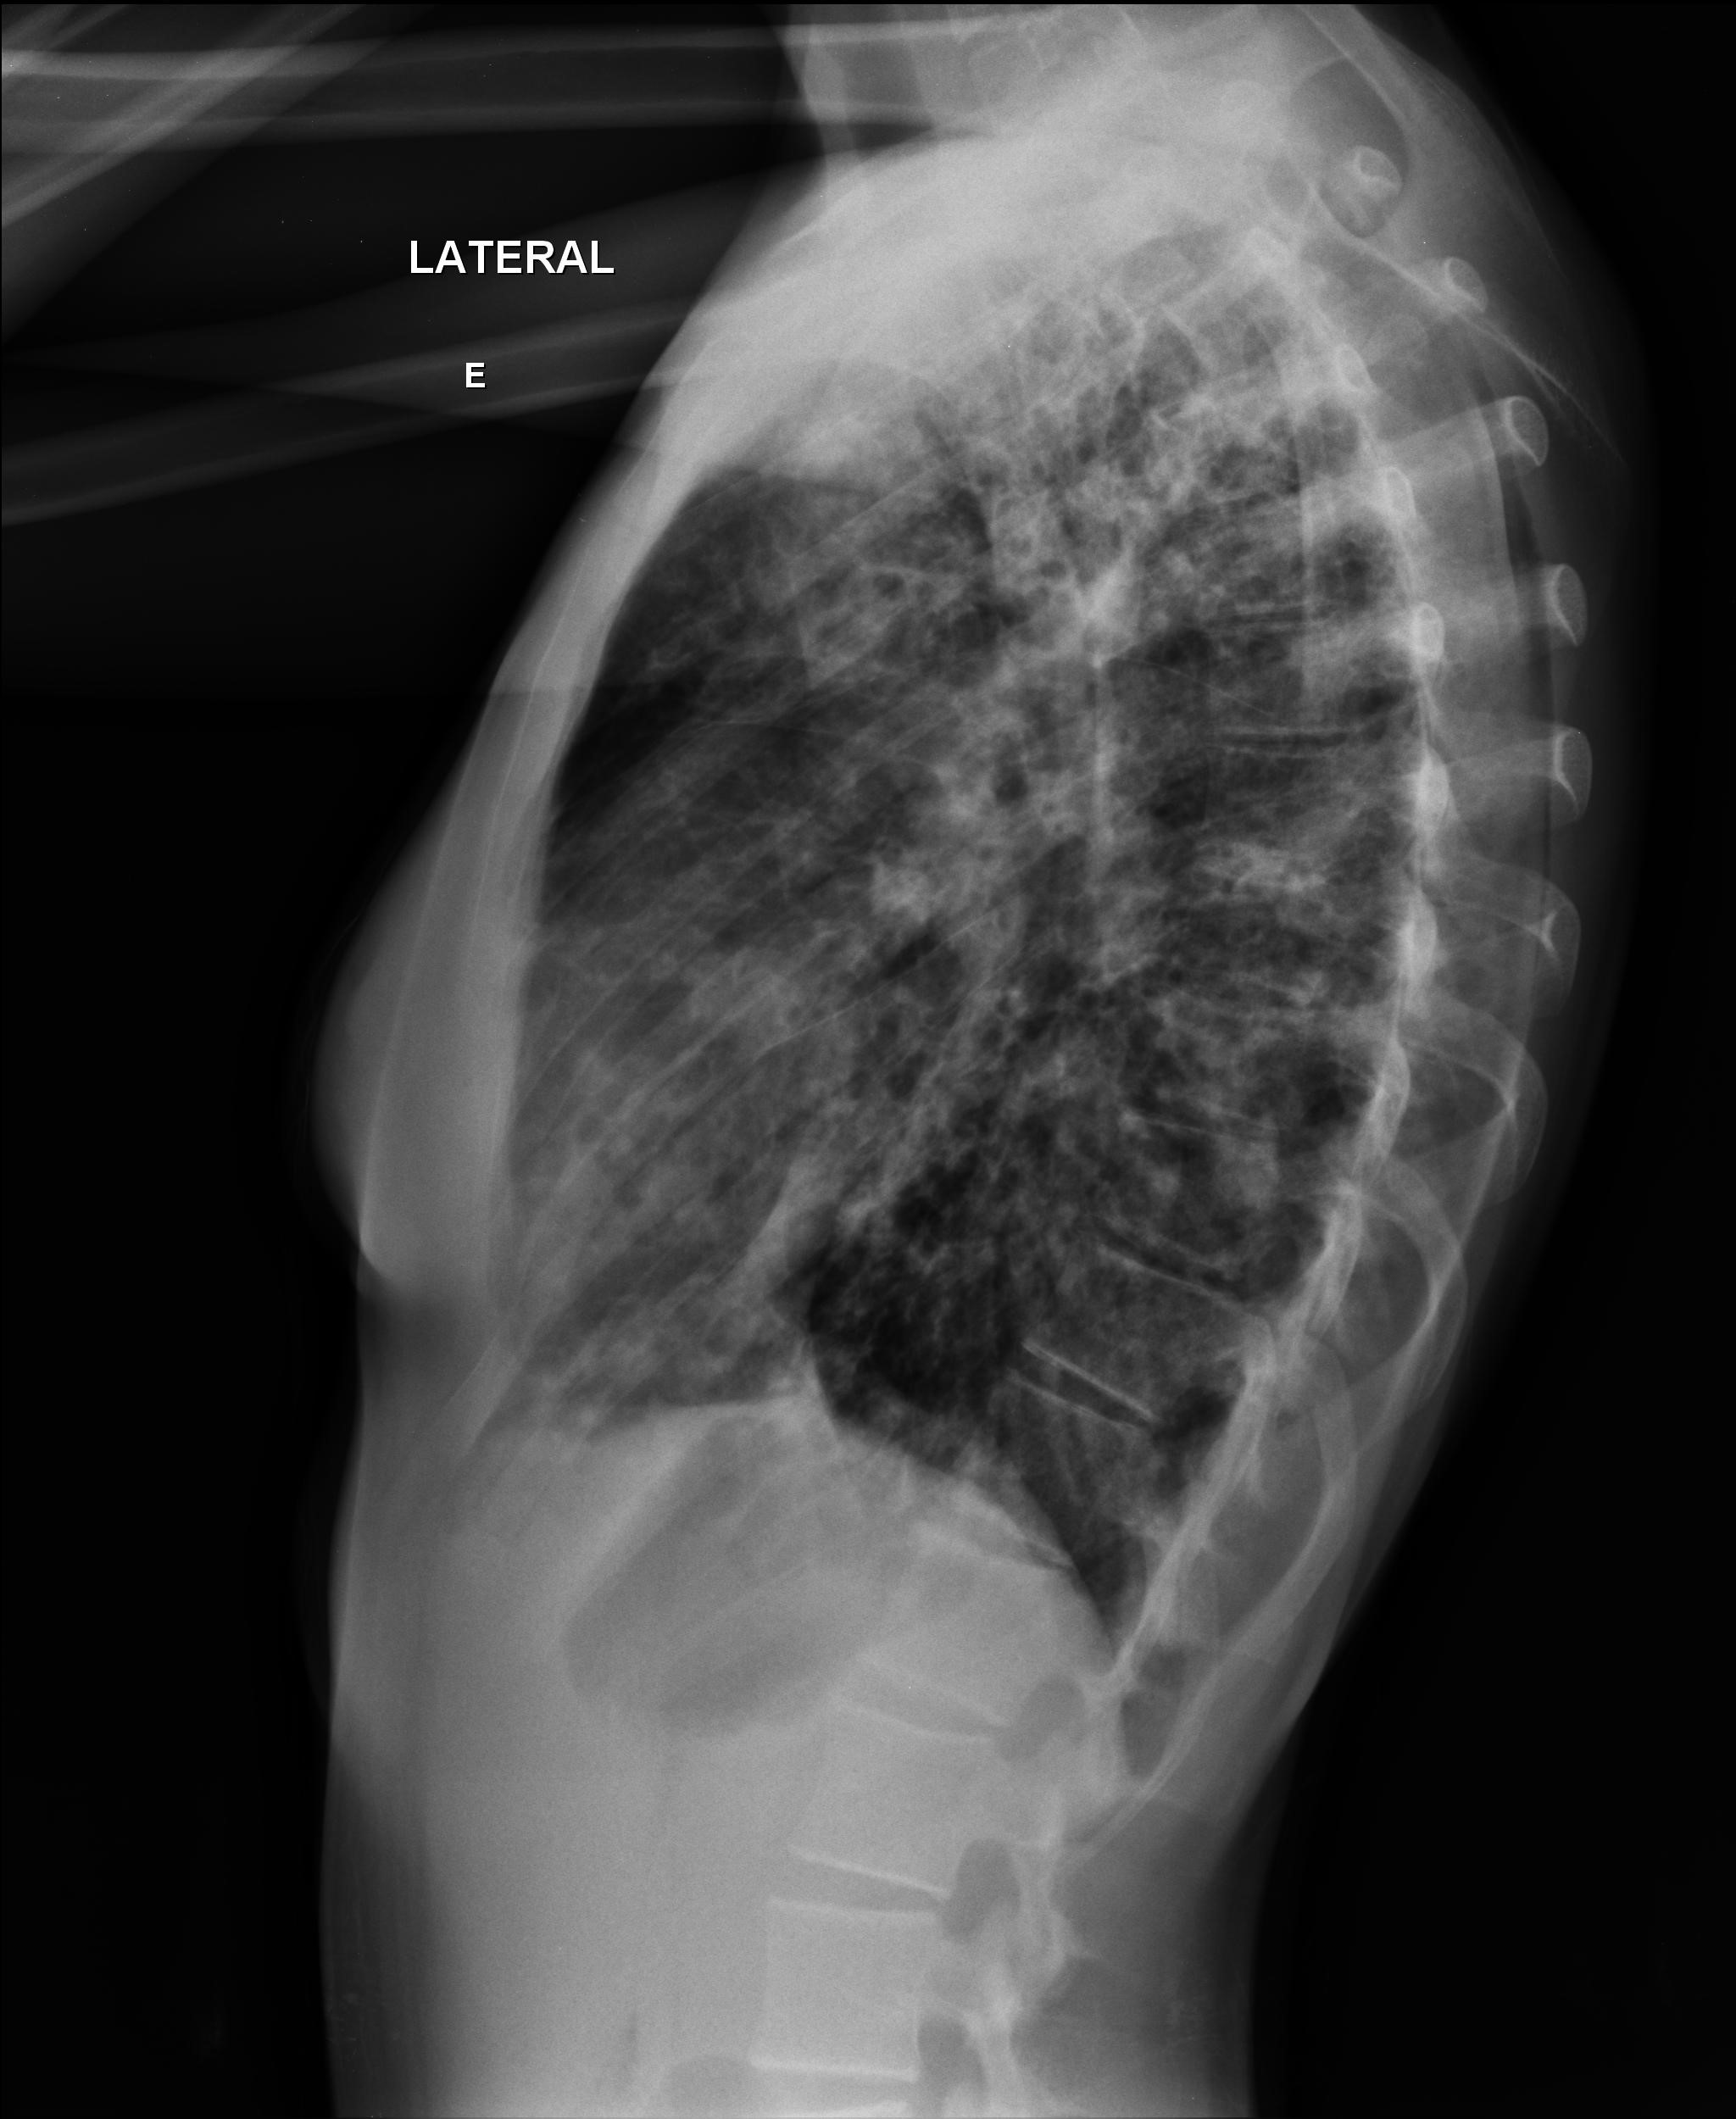

Caso Número 4/2018: “Uma sessão interativa de casos em radiologia torácica – Parte 1”

Caso relatado na Reunião de Discussão de Casos Clínicos do Hospital Universitário Prof. Polydoro Ernani de São Thiago, iniciada pelos Profs. Jorge Dias de Matos, Marisa Helena César Coral e Rosemeri Maurici da Silva, em julho de 2017. No dia 14 de junho de 2018, no auditório do HUPEST, realizou-se a apresentação e discussão do caso cujo registro é apresentado a seguir. Trata-se da discussão de onze casos em radiologia torácia, de forma interativa com a plateia, e assim ocorre também neste artigo.